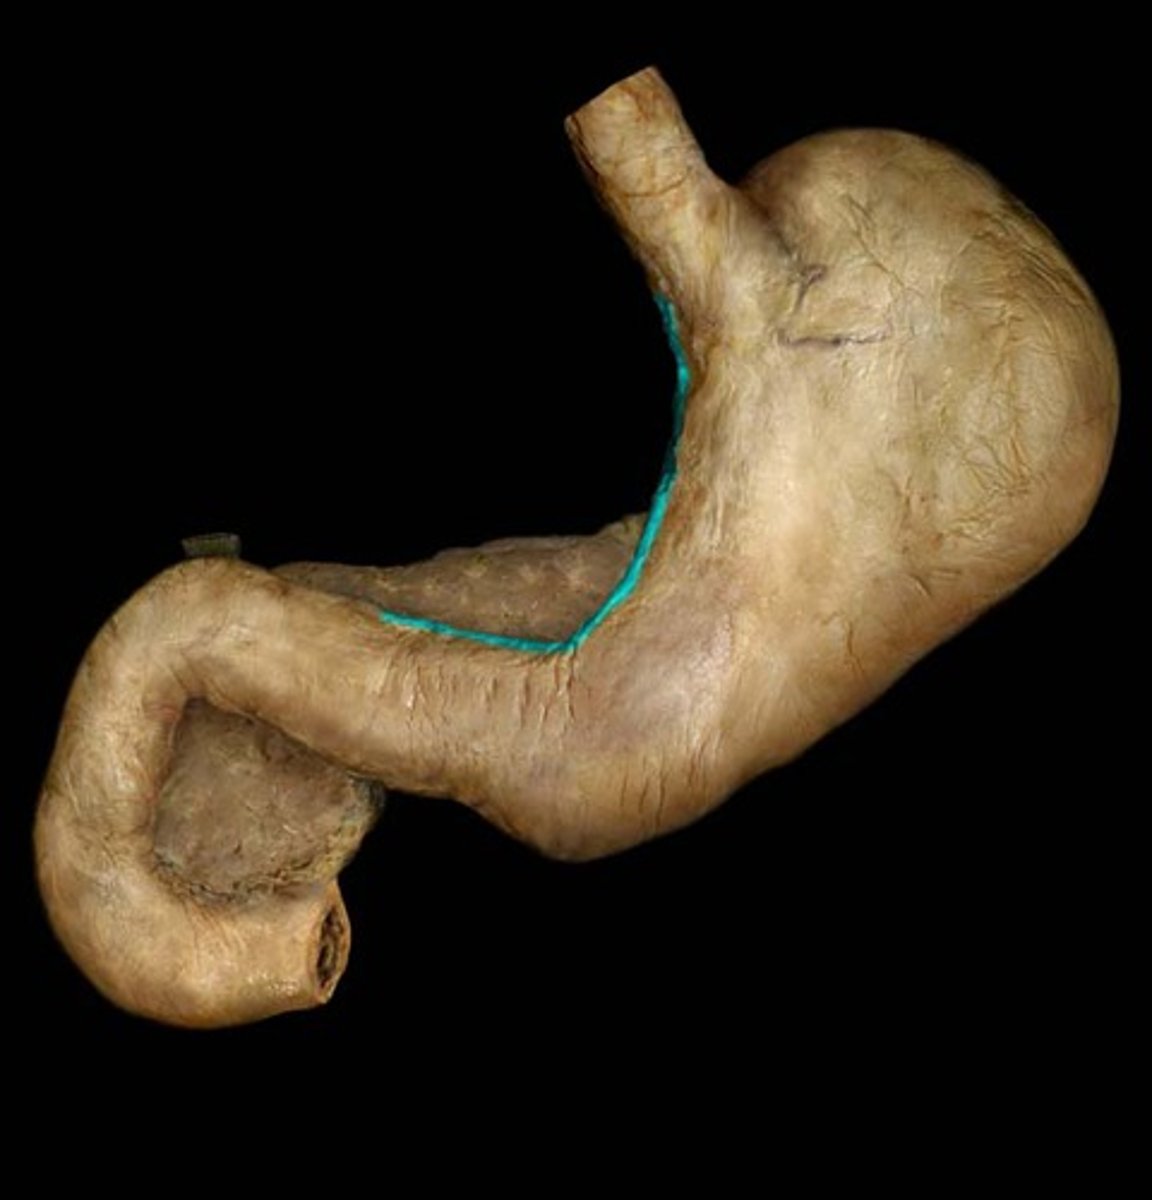

What is this?

Cardiac region of stomach

Fundus

Body of the stomach

Pylorus

Pyloric sphincter

Greater curvature

Lesser curvature